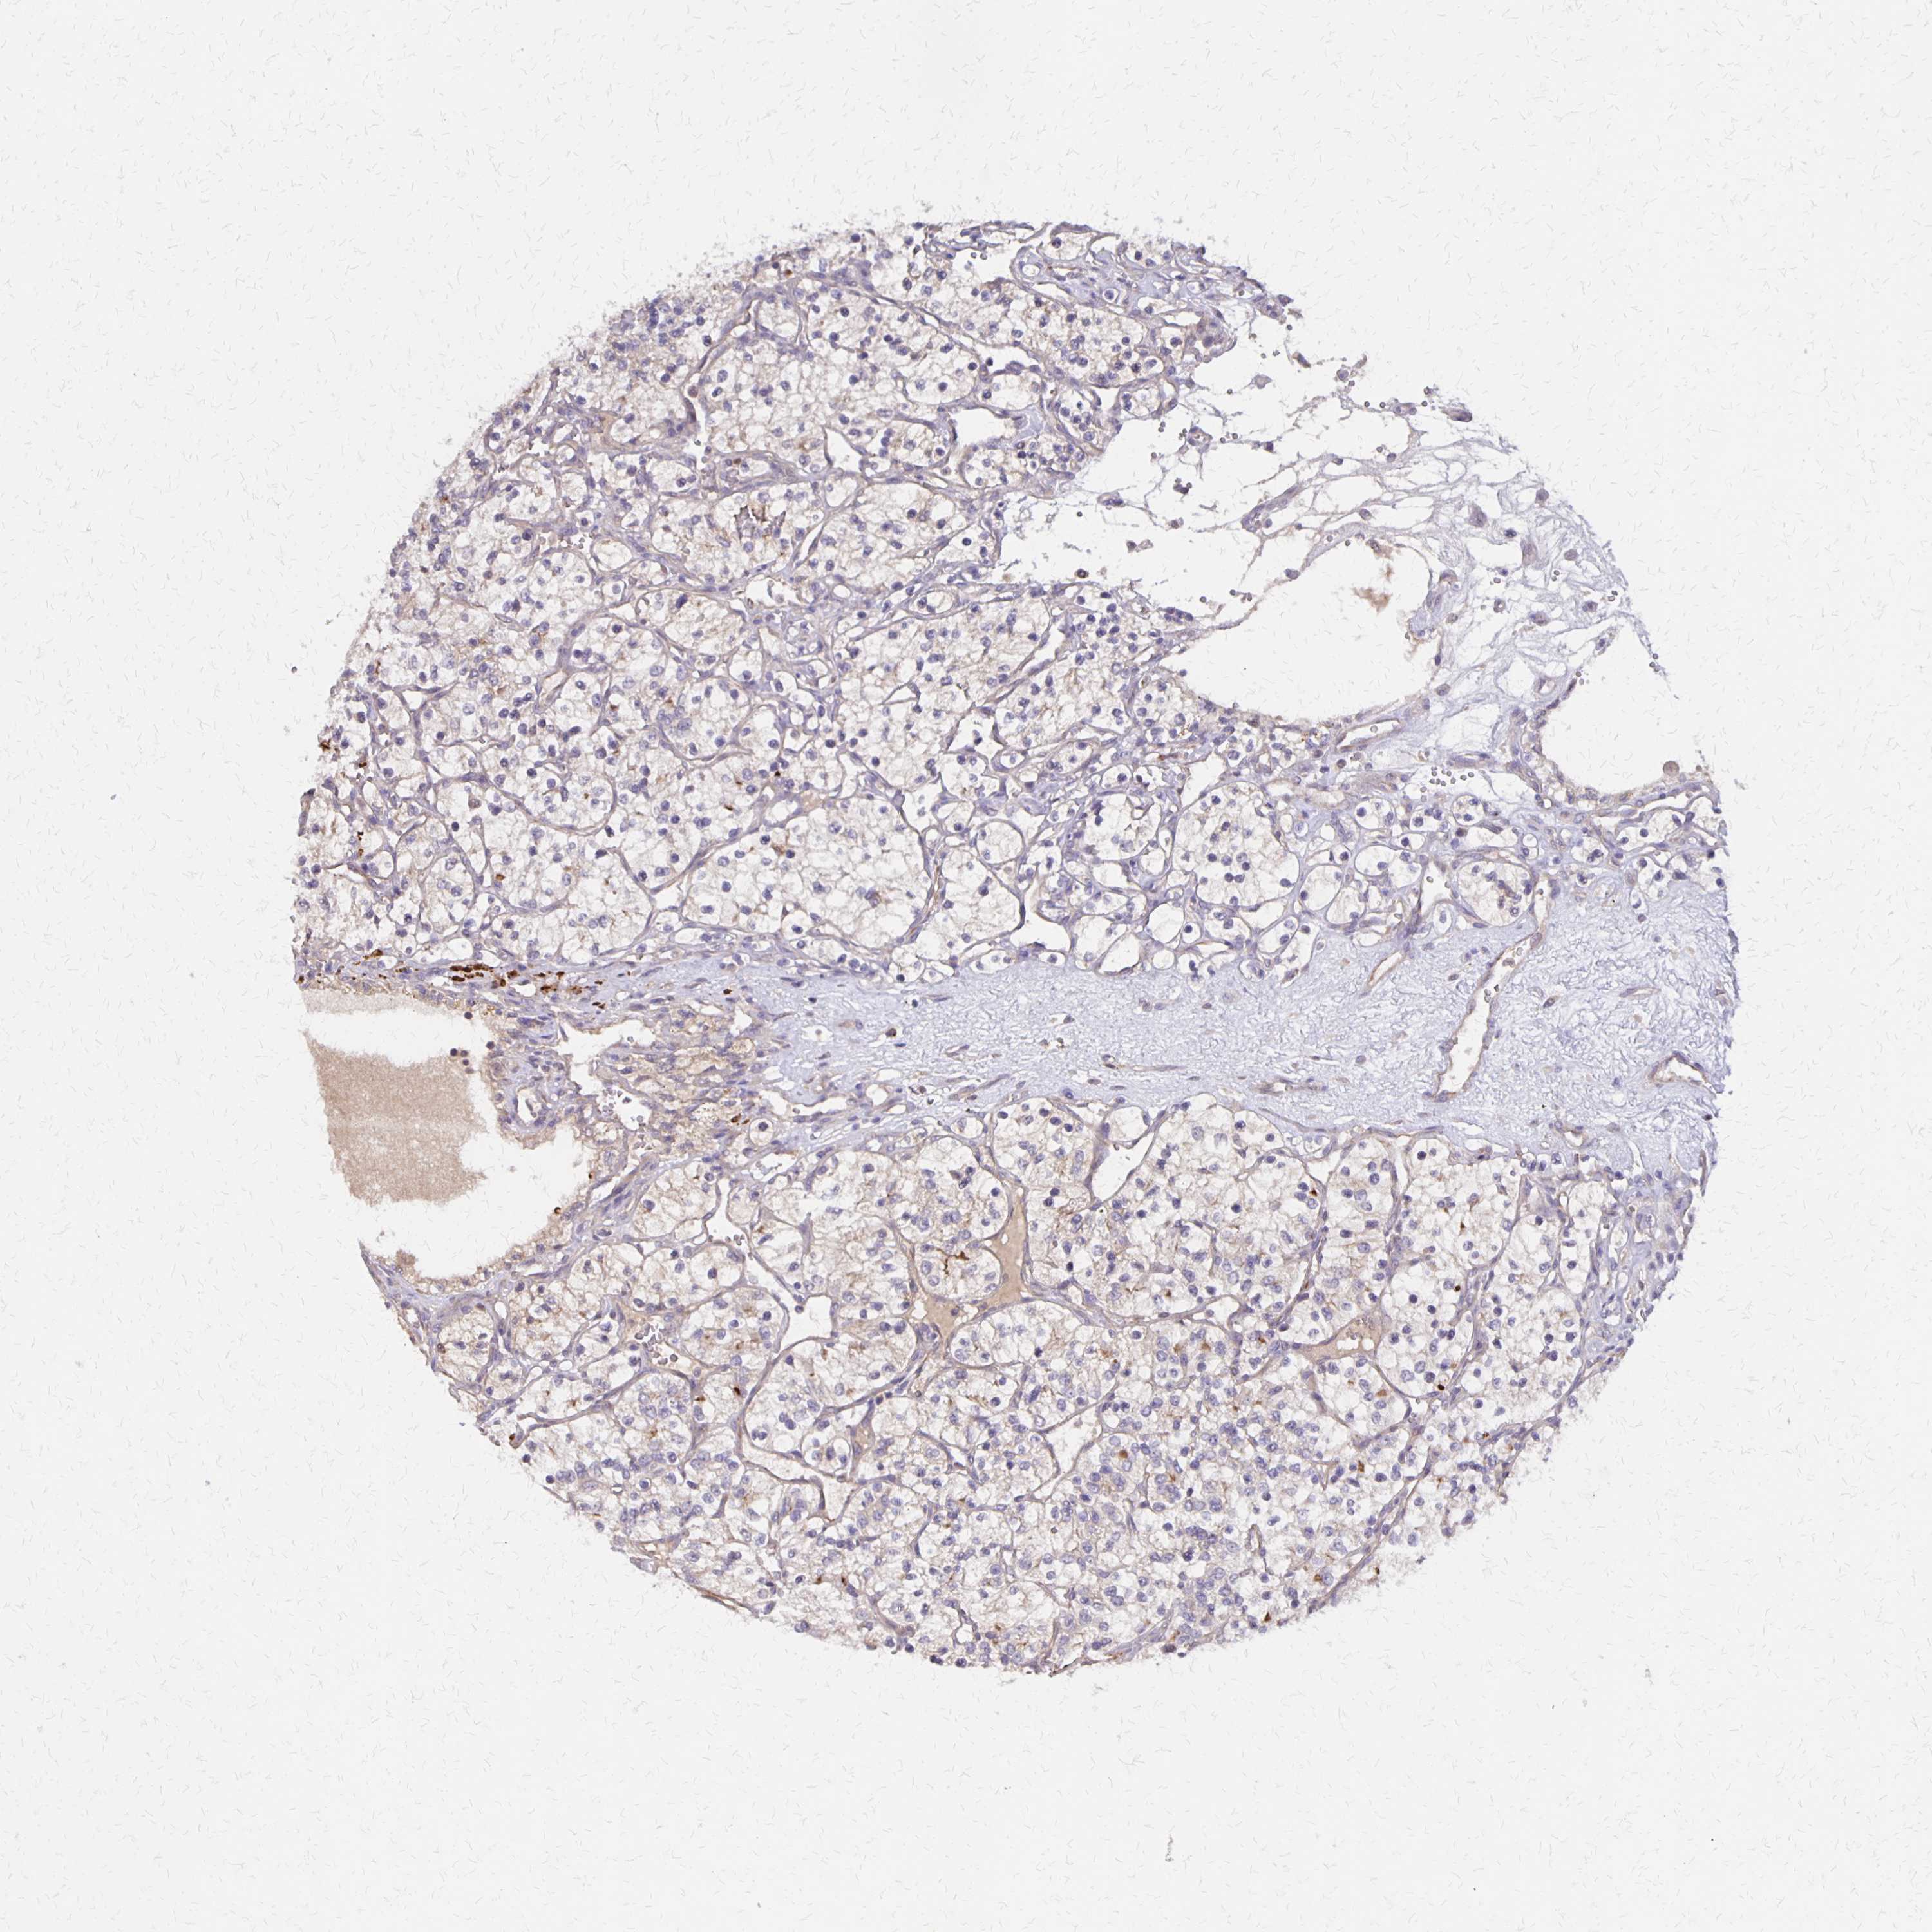

KIDNEY RENAL CLEAR CELL CARCINOMA (TCGA) - Interactive survival scatter ploti

The Survival Scatter plot shows the clinical status (i.e. dead or alive) for all individuals in the patient cohort, based on the same data that underlies the corresponding Kaplan-Meier plots. Patients that are alive at last time for follow-up are shown in blue and patients who have died during the study are shown in red.

The x-axis shows the expression levels (FPKM) of the investigated gene in the tumor tissue at the time of diagnosis. The y-axis shows the follow-up time after diagnosis (years). Both axes are complimented with kernel density curves demonstrating the data density over the axes. The top density plot shows the expression levels (FPKM) distribution among dead (red) and alive patients (blue). The right density plot shows the data density of the survived years of dead patients with high and low expression levels respectively, stratified using the cutoff indicated by the vertical dashed line through the Survival Scatter plot. This cutoff is automatically defined based on the FPKM cutoff that minimizes the p-score. The cutoff can be changed by dragging the vertical line or by entering a cutoff value in the square labeled "Current cut-off".

Under the Survival Scatter plot the p-score landscape (black curve; left axis) is shown together with dead median separation (red curve; right axis). Dead median separation is the difference in median mRNA expression between patients who have died with high and low expression, respectively. It is calculated as follows: median FPKM expression of dead patients with high expression - median FPKM expression of dead patients with low expression. This is intended to aid the user in visually exploring custom cutoffs and the associated p-scores and dead median separation.

Individual patient data is displayed and can be filtered by clicking on one or more of the category buttons on the top of the page. Categories describing expression level and patient information include: high, low, alive, dead, female, male and tumor stages. The scale of the x-axis can be toggled between linear and log-scale by clicking on the "x log" button. Mouse-over function shows TCGA ID, patient information and mRNA expression (FPKM) for each patient.

& Survival analysisi

Kaplan-Meier plots summarize results from analysis of correlation between mRNA expression level and patient survival. Patients were divided based on level of expression into one of the two groups "low" (under cut off) or "high" (over cut off). X-axis shows time for survival (years) and y-axis shows the probability of survival, where 1.0 corresponds to 100 percent.

NOG is not prognostic in Kidney Renal Clear Cell Carcinoma (TCGA)

Best expression cut offi

Based on the FPKM value of each gene, patients were classified into two groups and association between prognosis (survival) and gene expression (FPKM) was examined. The best expression cut-off refers the FPKM value that yields maximal difference with regard to survival between the two groups at the lowest log-rank P-value. Best expression cut-off was selected based on survival analysis .

When clicking on this number, the vertical dashed line indicating cut-off, the interactive survival plot, and the Kaplan-Meier curve will be adjusted to show results based on the best expression cut-off.

: 0.72

P scorei

Log-rank P value for Kaplan-Meier plot showing results from analysis of correlation between mRNA expression level and patient survival.

N/A

Average pTPM 2.2

Number of samples 521